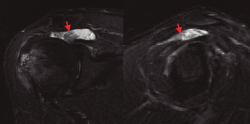

Figura 1. Imágenes en corte coronal y sagital de la ventana STIR de la RM, evidenciando rotura masiva del manguito rotador y la presencia de unas vellosidades grasas hipointensas en el seno de la bursa subacromial (señaladas mediante flechas).

En la resonancia magnética (RM) de los hombros, los citados cambios degenerativos con quistes subcondrales en la cabeza humeral y presencia de cambios inflamatorios en cabeza y troquíter eran evidentes, observándose el LA como una infiltración grasa con vellosidades en la cavidad articular hiperintensas en T1 y T2, con imágenes hipointensas en las ventanas STIR y supresión grasa. También se observó el acúmulo de líquido en la zona de la bursa subacromial (Figura 1), presentando en ocasiones una discreta migración proximal de la cabeza humeral. En ocasiones se evidenció también una alteración de la señal en los tendones del manguito rotador, compatibles en algún caso con roturas. En la RM de los casos de rodilla se evidenció el LA como un crecimiento de partes blandas en la bursa suprapatelar de intensidad compatible con la grasa, asociada a la presencia de derrame articular (Figura 2). Dicha masa era heterogénea, irregular, adherida al plano anterior.